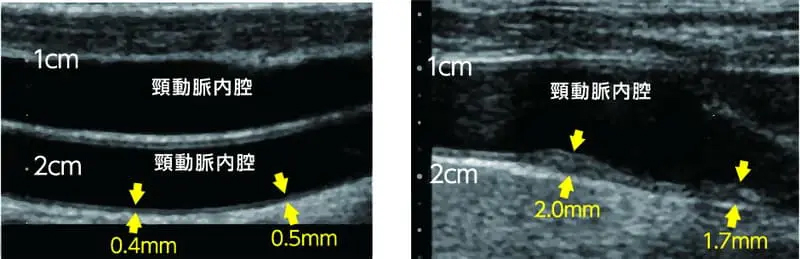

頸動脈エコーの図